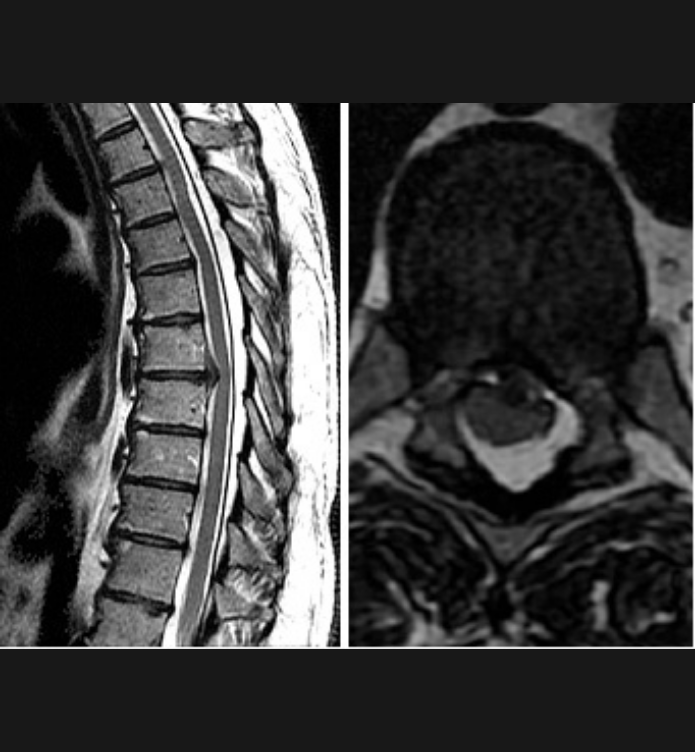

Basit Omurga ve Omurilik Anatomisi Omurga, 33 adet omur kemiğinden oluşur. Bu kemiklerin 7 tanesi boyun omuru, 12 tanesi sırt omuru, 5 tanesi bel omurudur. Beş tanesi birleşmiş olarak sakrum denilen kemiği ve 4 tanesi yine birleşmiş olarak koksiks denilen kuyruk sokumu kemiğini oluşturur. Omurganın görevi omuriliği korumak ve gövdeyi dik pozisyonda tutmak için destek […]